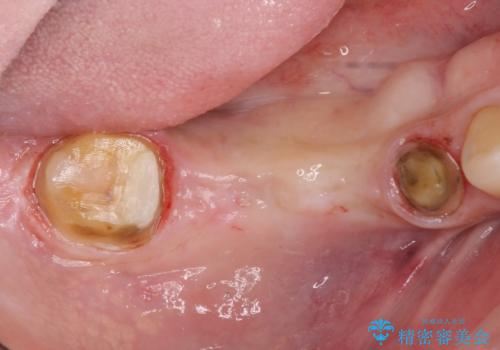

長いブリッジをインプラント補綴への変更

- 右下に入れた長いブリッジが噛むといたみ、改善を希望され来院されました。

長いブリッジは支台となる歯の過大な負担となることが多く、歯の破折や揺れ・痛みの原因となり得ます。

支台を増やし、残った歯の負担を減らし守るために欠損部位にインプラントを埋入し咬合力の負担に対応できる環境を整えます。